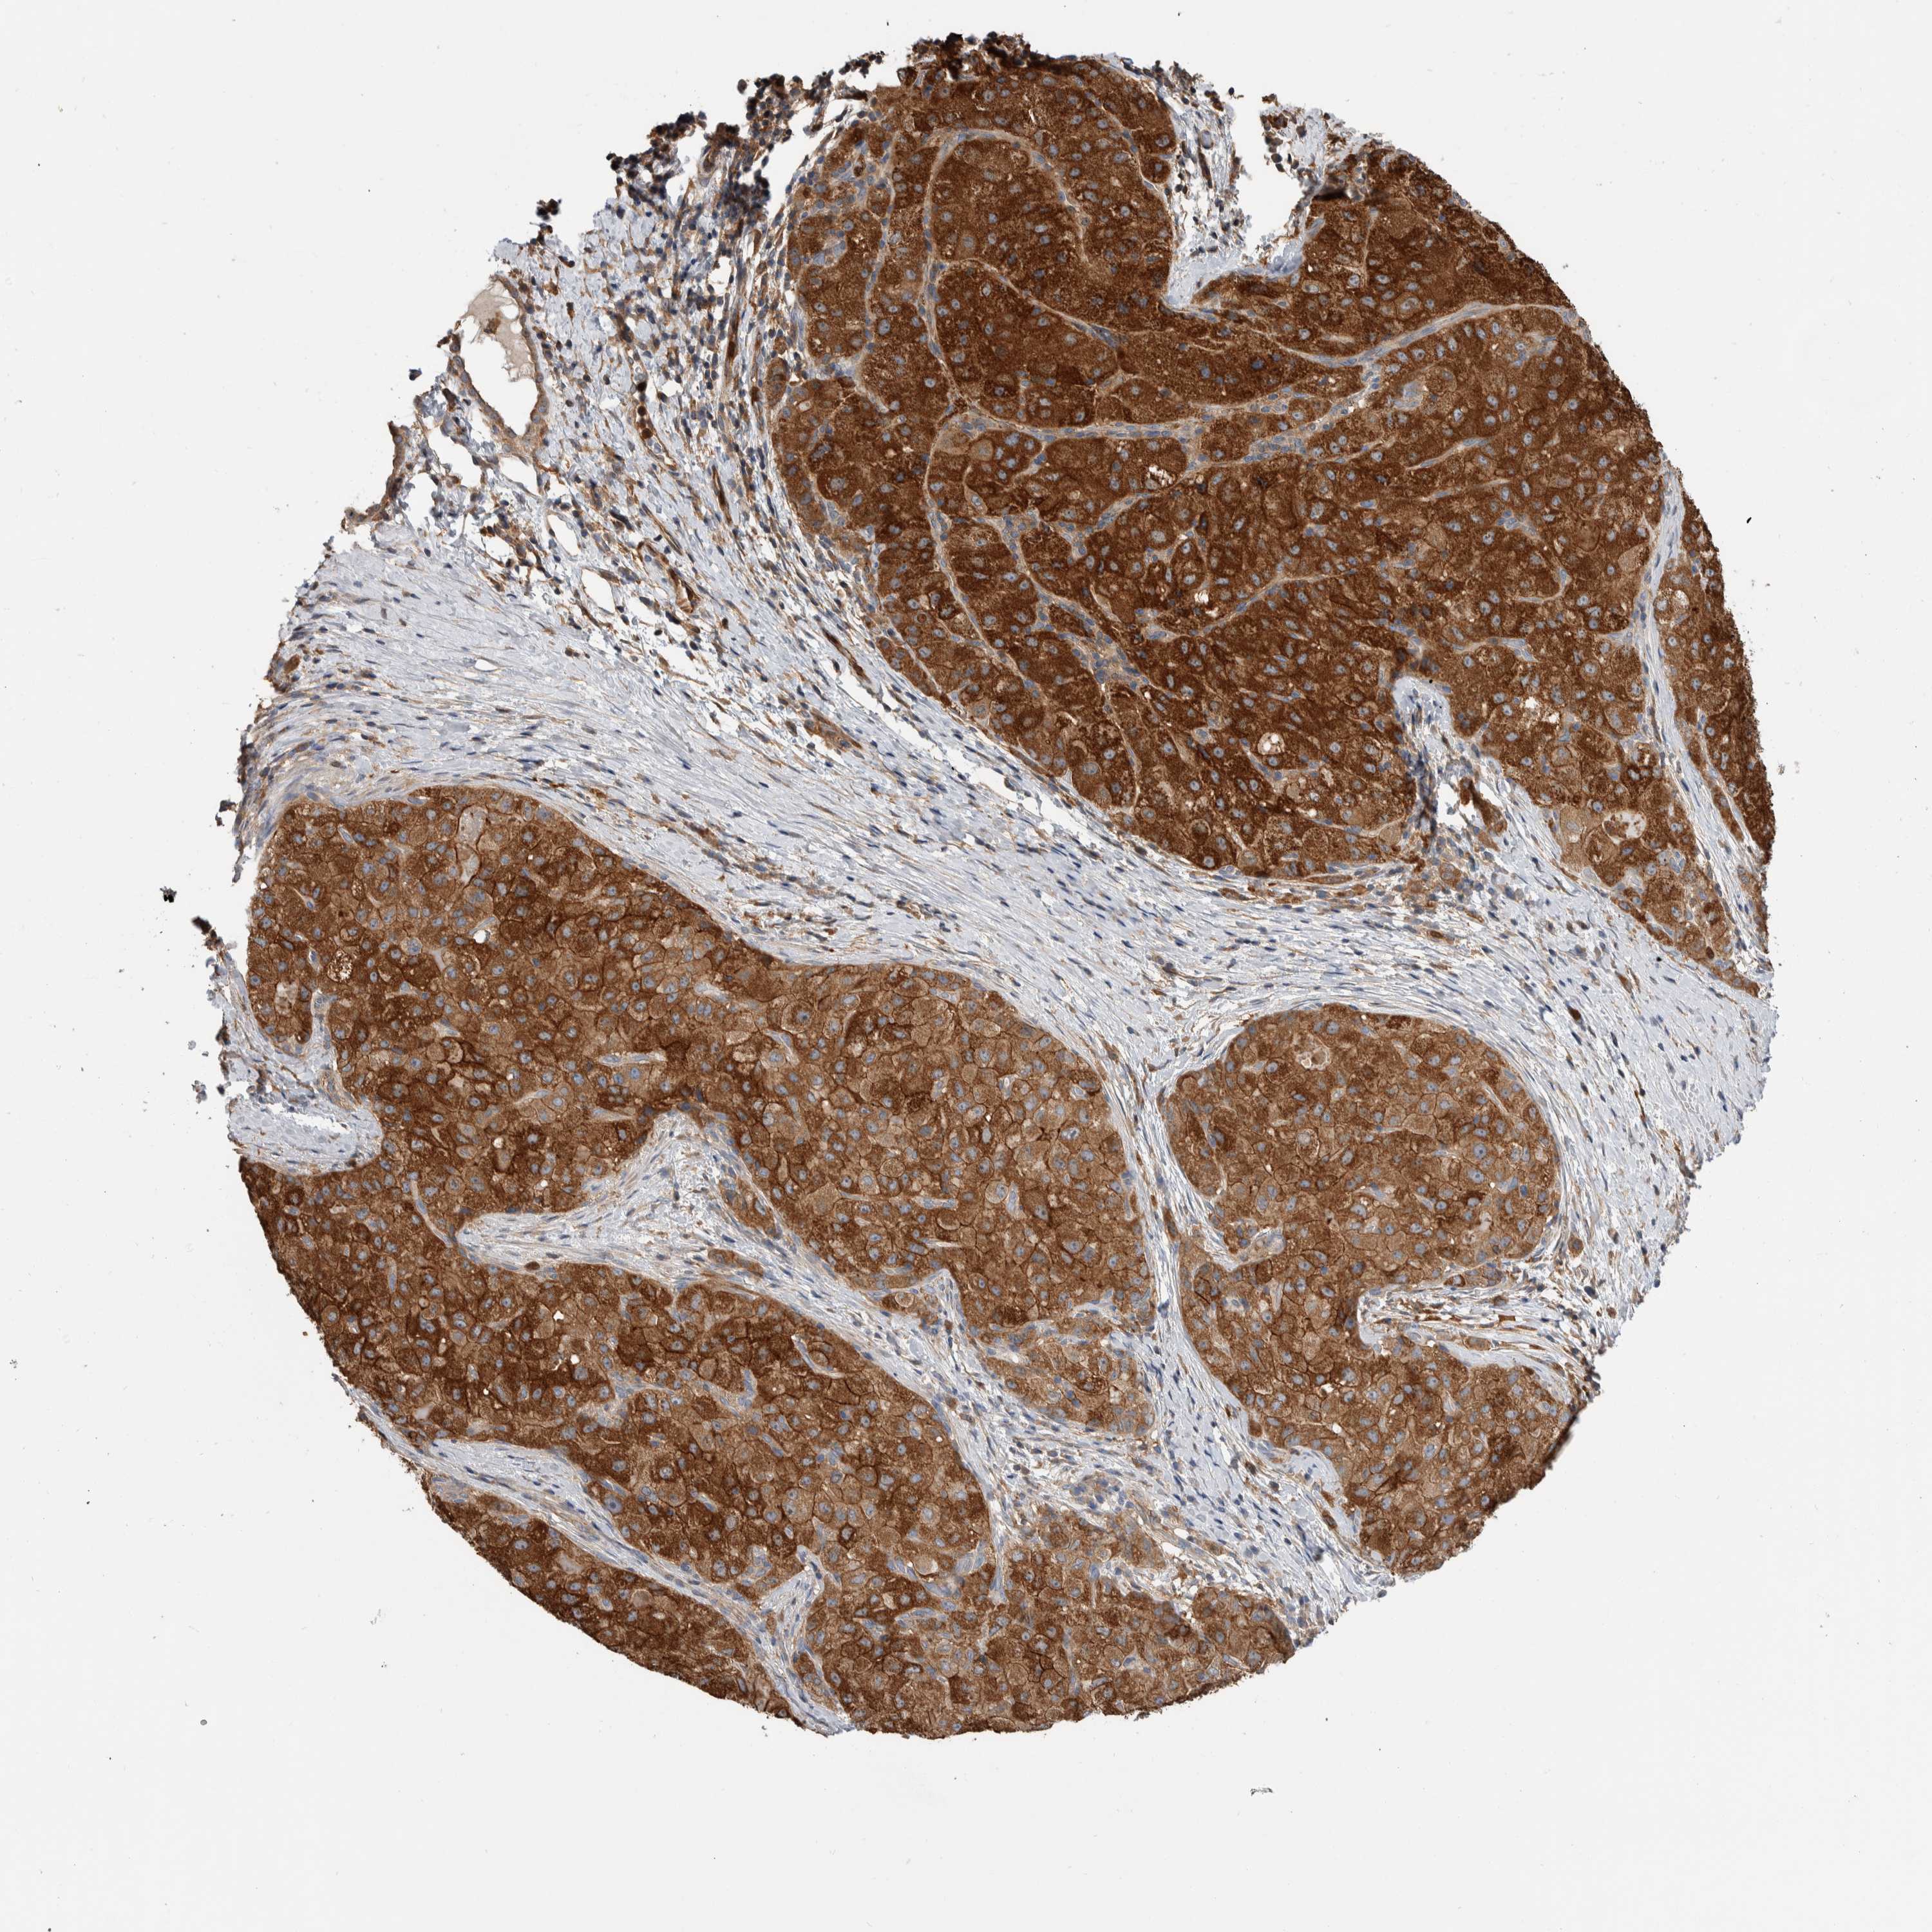

LIVER CANCER - Protein expressioni

A mouse-over function shows sample information and annotation data. Click on an image to view it in a full screen mode. Samples can be filtered based on level of antibody staining by selecting one or several of the following categories: high, medium, low and not detected. The assay and annotation is described here.

Note that samples used for immunohistochemistry by the Human Protein Atlas do not correspond to samples in the TCGA dataset.

Antibody stainingi

Antibody staining in the annotated cell types in the current human tissue is reported as not detected, low, medium, or high, based on conventional immunohistochemistry profiling in selected tissues. This score is based on the combination of the staining intensity and fraction of stained cells.

Each image is clickable and will lead to virtual microscopy that enables deeper exploration of all samples and also displays staining intensity scores, fraction scores and subcellular localization as well as patient and tissue information for each sample.

Antibody HPA023840

Antibody CAB012245

Staining

High

Medium

Low

Not detected

Intensity

Strong

Moderate

Weak

Negative

Quantity

>75%

75%-25%

<25%

None

Location

Nuclear

Cytoplasmic/membranous

Cytoplasmic/membranous,nuclear

Cholangiocarcinoma

Carcinoma, Hepatocellular, NOS